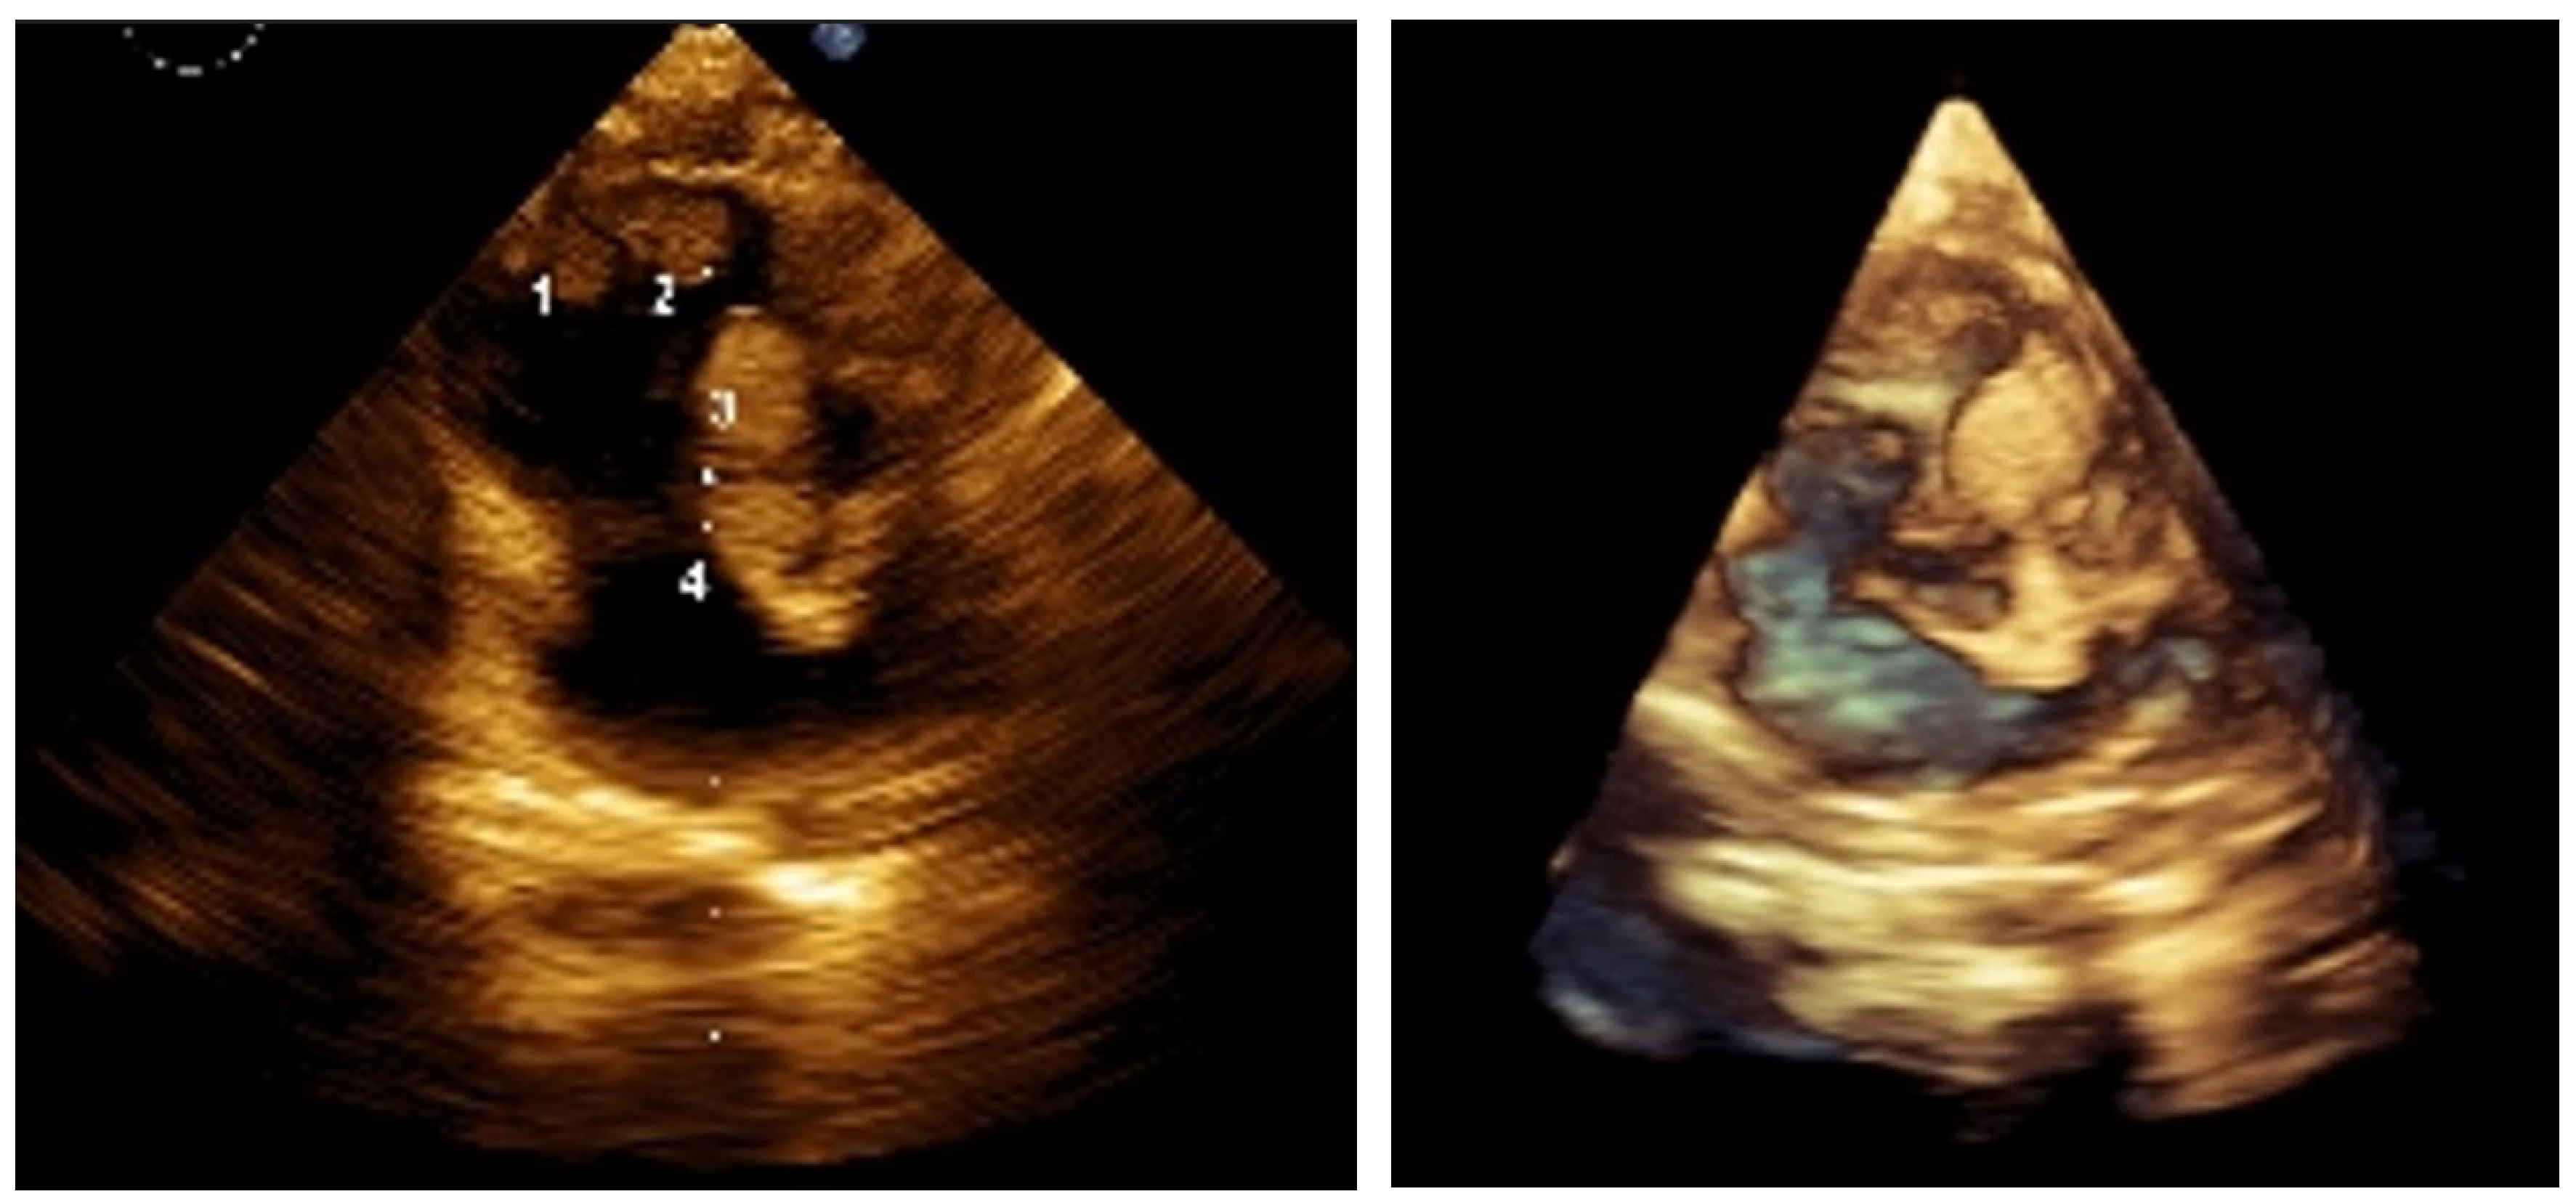

Figure 1.

2D and 3D images of the lesions before treatment. Reports suggest approximately 60% of children with TSC present with cardiac rhabdomyomas (CRs). These tumors can undergo spontaneous regression, although the underlying mechanisms are not fully understood. Partial regression of CRs has been reported in about 50% of cases, and with complete resolution in approximately 18% [

1]. In most cases, treatment is not required as the lesions regress spontaneously. However, patients with left ventricular outflow tract obstruction or refractory arrhythmias may require surgical resection. Prognosis depends on the number, size, and location of lesions, as well as the presence of associated anomalies. Overall, despite the potential for regression, cardiac manifestations present a clinical problem in about one-third of cases. A multidisciplinary team—including a clinical geneticist, pediatric cardiologist, neonatologist, and pediatric oncologist specializing in solid tumors—managed the case of a 1-month-old premature infant diagnosed with TSC according to international criteria. The infant was born at 35 weeks’ gestation, weighing 1980 g and measuring 44 cm, and was one of four siblings; the mother had experienced three spontaneous abortions. The neonatal period was complicated by infection and respiratory failure. Diagnosis occurred at 1 month due to a detected heart murmur. Echocardiography revealed cardiac rhabdomyomatosis (

Figure 1), prompting clinical and genetic evaluation. A